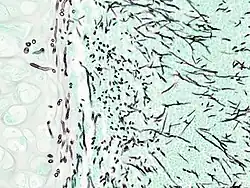

On microscopy, Aspergillus species are reliably demonstrated by silver stains, e.g., Gridley stain or Gomori methenamine-silver.[27] These give the fungal walls a gray-black colour. The hyphae of Aspergillus species range in diameter from 2.5 to 4.5 μm. They have septate hyphae,[28] but these are not always apparent, and in such cases they may be mistaken for Zygomycota.[27] Aspergillus hyphae tend to have dichotomous branching that is progressive and primarily at acute angles of around 45°.[27]

Angioinvasive pulmonary aspergillosis -

Angioinvasive pulmonary aspergillosis (closeup) -